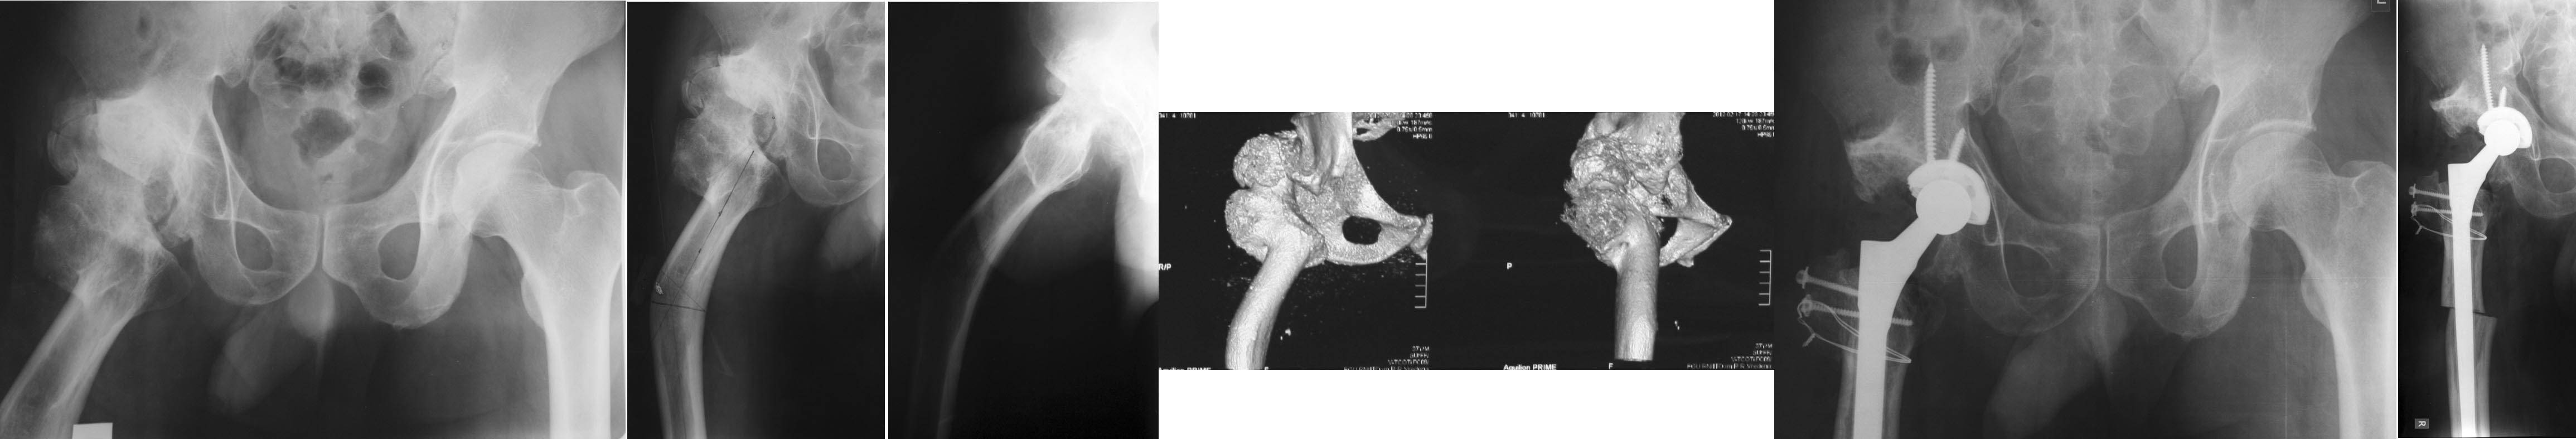

Пациентка 41 год, нормального телосложения, правосторонний диспластический коксартроз Crowe IV состояние после опорной остеотомии по Илизарову более 20-ти лет назад. Жалобы на боль в паху, пояснице, ограничение движений, хромоту. Относительное укорочение правой н.к. 2-3 см. Абсолютное периудлинение правого бедра 5-6 см (по данным КТ). Планируем укорачивающую резекцию бедра с транспозицией большого вертела. В литературе широко описаны аналогичные случаи эндопротезирования после остеотомии по Schanz, однако в отличие от Илизаровской остеотомии, без абсолютного переудлинения бедра и без деформаций канала на уровне с/3 диафиза. Ув. коллеги кто сталкивался с подобными случаями? Будем рады техническим и тактическим советам.

Уважаемый Игорь, ситуация непростая, и мы с ней сталкиваемся часто, к сожалению. Чашку целесообразно устновить в анатомическую позицию, потребуется двойная остеотомия бедра на уровне деформаций с установкой конической ножки Вагнера, проксимальный отдел с ягодичными мышцами лучше фиксировать сбоку, как по методике Paavilainen'a, таким образом Вы сможете избежать удлинения. Но.... Скорее всего нужен будет Вагнер не конический, а ревизионный с большим оффсетом, а это уже проблема при закрытии раны.... Поэтому надо очень тщательно спланировать все эти шаги. Любой другой вариант может не позволить исправить все деформации либо не обеспечит должной стабильности.